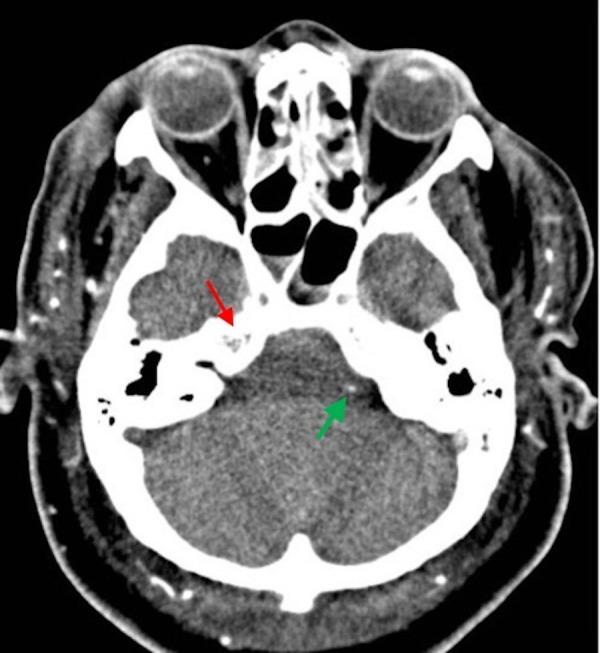

Introduction Brain death (BD) is the irreversible termination of the functioning of the brain. The diagnosis should be first made by clinical criteria and confirmed by using paraclinical confirmatory techniques (ancillary tests). While conventional brain angiography remains the standard method of choice, computed tomography angiography (CTA) has emerged as an alternative method. In this study, we tried to evaluate the accuracy of CTA for the diagnosis of BD. Methods In this study, we included nine patients with a clinical diagnosis of BD, confirmed by electroencephalography (EEG). CTA was then performed to compare the results. Results The most frequent cause for BD was multiple trauma (7/9) in our patients, followed by aneurysm rupture and brain infarct. CTA examination in all patients showed opacification of extracranial arteries and major branches of external carotid artery (ECA), including superficial temporal arteries (STAs), while no opacification was observed in the internal carotid arteries (ICA) including and beyond the cavernous segment, middle cerebral arteries (MCAs), anterior cerebral arteries (ACAs), distal vertebral arteries (VAs), and basilar artery (BA). Moreover, no opacification was observed in the internal cerebral veins (ICVs) or great cerebral vein (GCV). Conclusion The accuracy rate of CTA in the detection of intracranial circulatory arrest was 100%. CTA examinations confirmed BD diagnoses in all patients who had clinical and EEG BD diagnoses, and no confliction between CTA findings and clinical diagnoses was observed.

在我们的患者中,导致脑死亡最常见的原因是多发性创伤(7/9),其次是动脉瘤破裂和脑梗死。所有患者的CTA检查均显示颅外动脉和颈外动脉(ECA)的主要分支显影,包括颞浅动脉(STA),而在包括海绵窦段及其远端的颈内动脉(ICA)、大脑中动脉(MCA)、大脑前动脉(ACA)、椎动脉远端(VA)和基底动脉(BA)中未观察到显影。此外,在大脑内静脉(ICV)或大脑大静脉(GCV)中也未观察到显影。